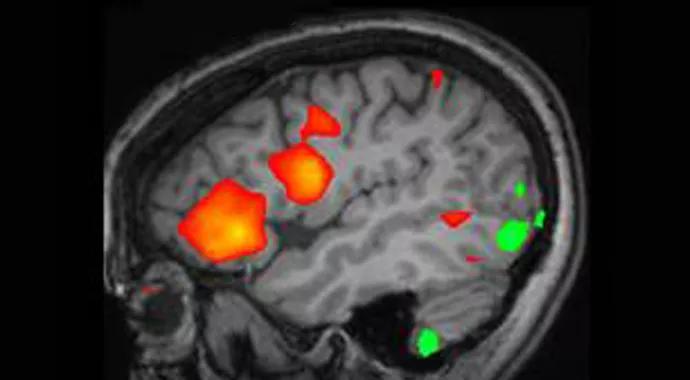

FIGURE 1. Schematic illustration of cortical activation revealed with functional MRI within the left basal frontal lobe and anterior insula. Areas of interest are superimposed on sagittal and axial images of the patient’s structural MRI. Red indicates activation; green indicates deactivation.

Studies of focal epileptic spikes caused by different types of brain pathologies have shown reliable activations in the fMRI BOLD signal within the expected location of the epileptogenic focus. In addition, these studies reveal areas of activation and deactivation at locations distant from the pathological focus, and thus provide a unique glimpse into the underlying networks of brain activity. The significance of distant responses in the study of brain connectivity and pathological epileptic networks is one of the issues under active investigation at Cleveland Clinic’s Epilepsy Center.